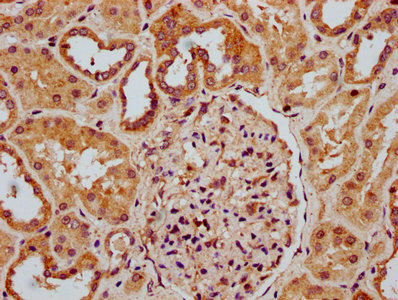

IHC image of CSB-PA019801LA01HU diluted at 1:300 and staining in paraffin-embedded human kidney tissue performed on a Leica BondTM system. After dewaxing and hydration, antigen retrieval was mediated by high pressure in a citrate buffer (pH 6.0). Section was blocked with 10% normal goat serum 30min at RT. Then primary antibody (1% BSA) was incubated at 4°C overnight. The primary is detected by a biotinylated secondary antibody and visualized using an HRP conjugated SP system.